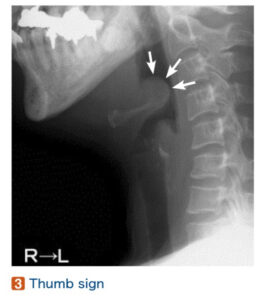

①急性喉頭蓋炎(声門上炎)

| 疫学 | 3〜6歳、成人に好発 |

| 病態 | 主に細菌感染によって喉頭蓋が蜂巣炎を起こして腫脹し、致命的な気道閉塞をもたらしうる緊急疾患。咽頭痛発症から呼吸苦出現までの時間が早いと緊急性が高い! ※気道閉塞のリスクあるため、仰臥位にしない(CTは危険) |

| 原因菌 | インフルエンザ桿菌(Hib)、レンサ球菌、肺炎球菌、黄色ブドウ球菌 |

| 症状 | ①咽頭痛(91%):喉頭蓋の炎症 ②嚥下障害(82%)、流涎(22%):咽頭狭窄 ③吸気性呼吸困難(37%)、声の変化(33%):喉頭蓋浮腫 ※窒息直前までSpO2は正常であることがほとんど ④発熱(26%):炎症のため |

| 所見 | 視診:咽頭痛を訴えるが咽頭所見に乏しい(症状と口腔所見の解離!) ※扁桃周囲膿瘍に合併することもあるため咽頭に所見があっても否定できない! ※舌圧子や喉頭鏡による咽頭部診察は嘔吐反射により窒息を誘発するため禁忌! 触診:舌骨部の圧痛 聴診:吸気性喘鳴(stridor) |

| 検査 | 【血液検査】 白血球数・CRPの上昇を認めることが多い 【画像検査】 喉頭高圧X線側面像:thumb sign うつ伏せで頸部造影CT:矢状断像で腫大した喉頭蓋(vallecula sign、thumb sign) |

| 診断 | 喉頭内視鏡で喉頭蓋の発赤・腫脹を確認![]() |

| 治療 | ![]() ①気道緊急が疑われる場合、気管挿管(緊急時は外科的気道確保) ②第3世代セフェム系点滴静注 例:CTRX2g/日 7〜10日間 例:CEZ1g/日 7〜10日間 ③ステロイド点滴静注 例:メチルプレドニゾロン(ソルメドロール®)1mg/kg+生食100mL ![]() |